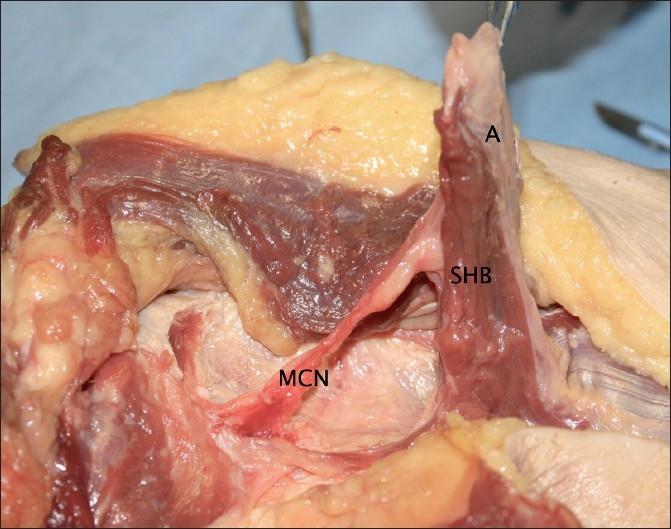

The short head of biceps brachii has been the subject of little investigation when compared to the long head or distal biceps tendons. The aim of this study was to dissect and describe the origin and proximal portion of the short head of biceps brachii.

Three left and two right (n = 5) fresh-frozen human cadaver shoulders were dissected and the proximal short head was measured and photographed.

The origin of the short head of biceps consisted of muscle fibres attaching directly to the tip of the coracoid process, with a thin, tendinous aponeurosis covering its anterior surface, rather than a true tendon as previously described.

The short head of biceps does not attach to the coracoid process via a true tendon. These findings have implications for procedures that utilise the short head of biceps.

与肱二头肌长头或远端肌腱相比,肱二头肌短头很少受到研究。本研究的目的是解剖并描述肱二头肌短头的起点和近端部分。

解剖了5具新鲜冷冻的人体尸体肩部(3例左侧,2例右侧),对近端短头进行测量并拍照。

肱二头肌短头的起点由直接附着于喙突尖端的肌纤维组成,其前表面覆盖着一层薄的腱膜,而非如先前所述的真正肌腱。

肱二头肌短头并非通过真正的肌腱附着于喙突。这些发现对涉及肱二头肌短头的手术具有启示意义。